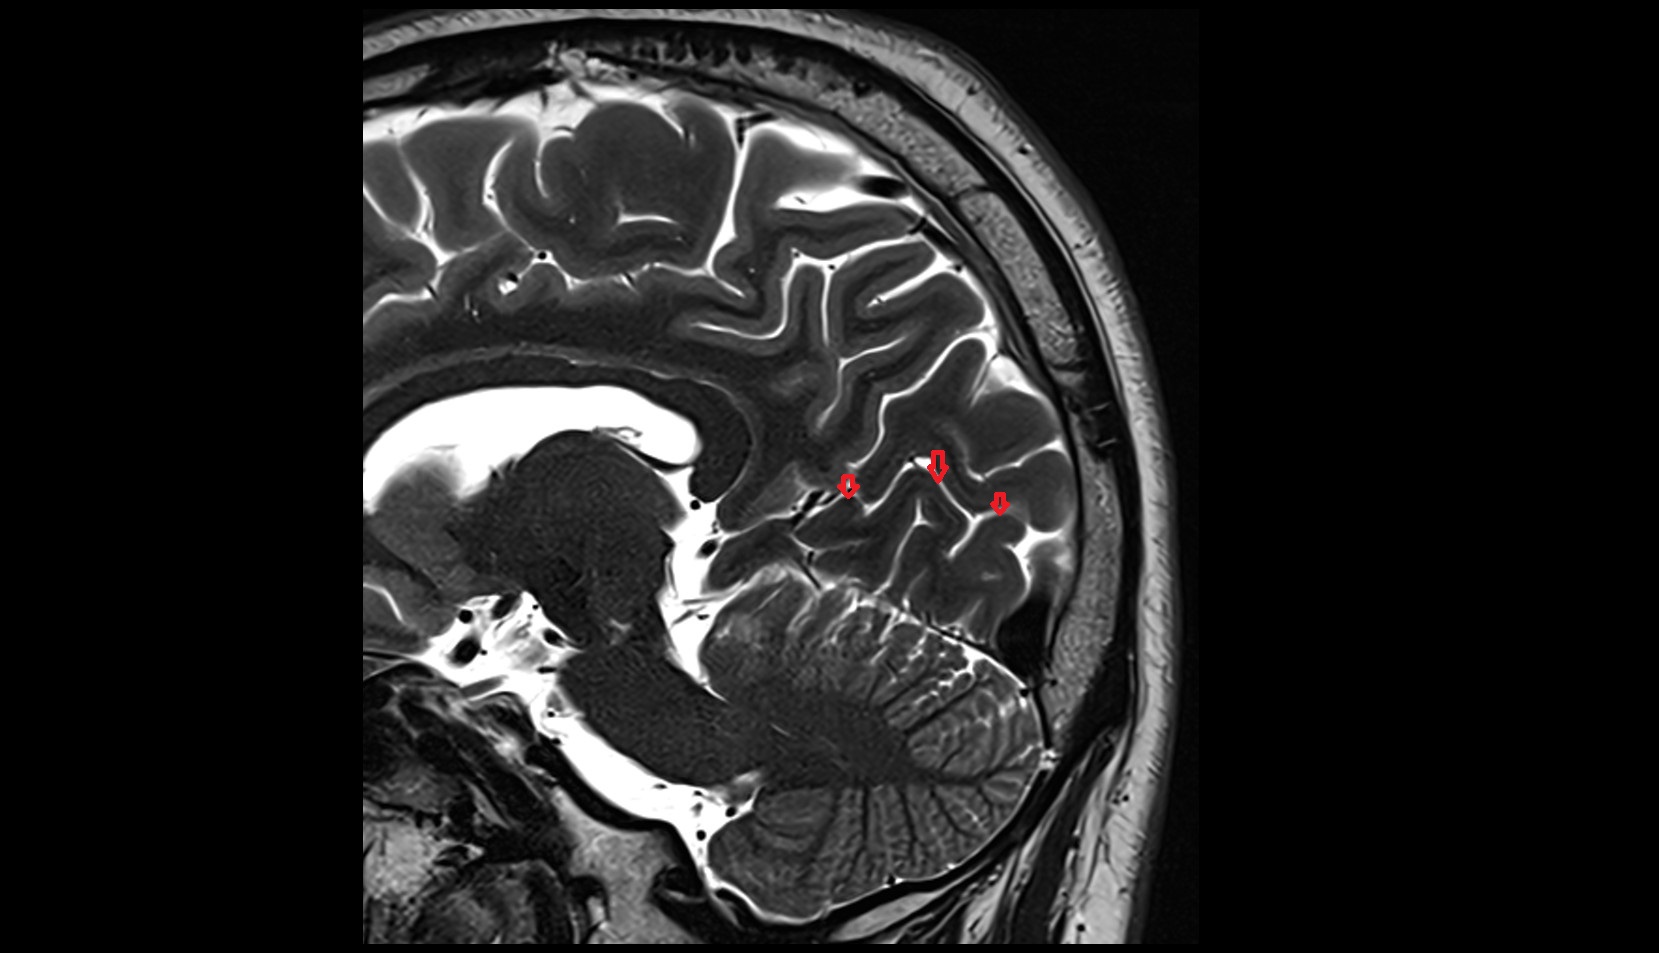

- Median aperture of fourth ventricle (foramen of Magendie)

- Lateral aperture of fourth ventricle (foramen of Luschka)

- Cerebral aqueduct

- Superior opening of cerebral aqueduct